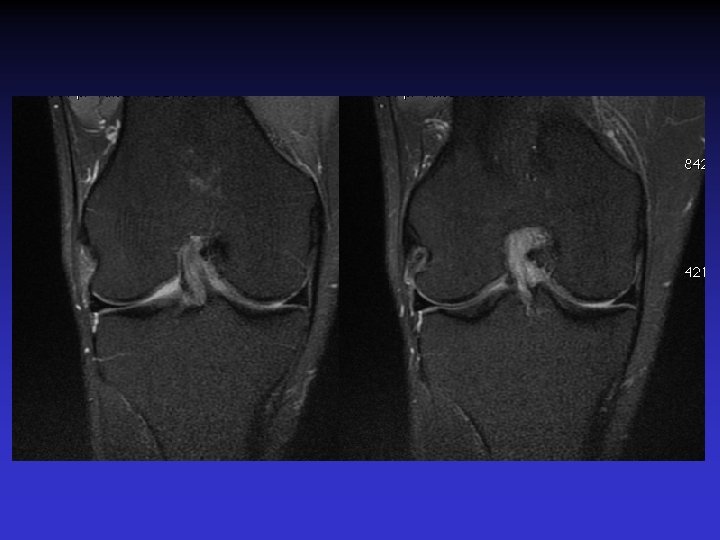

ATTEINTE BILATERALE • Non exceptionnelle • Concomitante ou décalée dans le temps

Mme S… 60 ANS DROIT

Mme S… 60 ANS GAUCHE